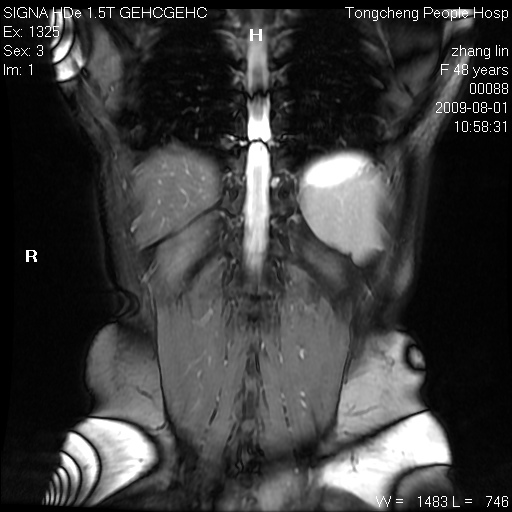

女,48岁。健康体检,彩超发现右肾占位性病变。平素健康。

临床诊断:右肾占位性病变,性质待定(囊肿?肿瘤?)。

上中腹部mr平扫+增强扫描,图像如下:

右肾上极见一类圆形病灶,t1wi呈等信号t2wi呈等高混杂信号,三期增强无强化,边界清---考虑囊肿出血。